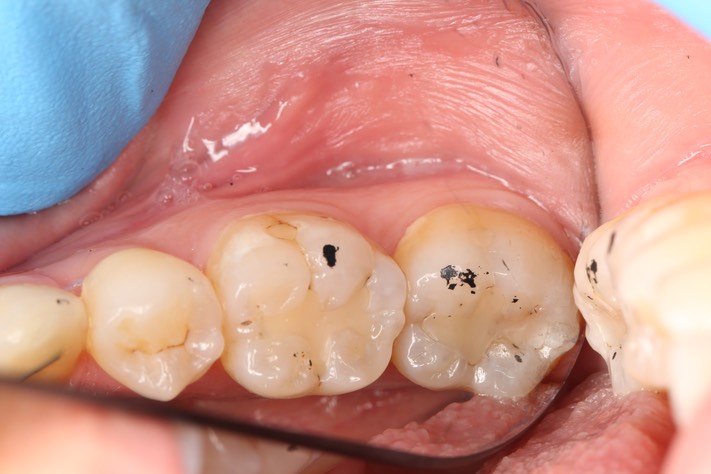

Chris Woo #18 - 19 pre-op